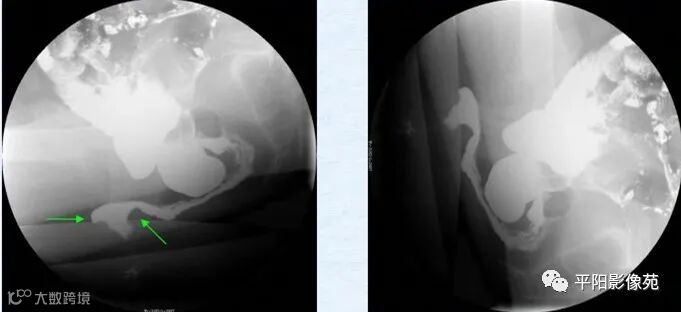

直肠内套叠(internal rectal intussusception,IRI)又称直肠隐性脱垂。有两种情况,①直肠内黏膜套叠:增粗而松弛的直肠黏膜脱垂,在直肠内形成约3mm的环形套叠;②直肠内全层黏膜套叠:脱垂的直肠黏膜形成的环形套叠厚度>5mm。按套叠的部位分为:近段套叠、远段套叠、直肠套入肛管等3种。套叠可合并其他异常,或多发或多重套叠。(图3)

图3 直肠内黏膜紊乱、堆积并套入肛管内

直肠外脱垂(external rectal prolapse,ERP):也成直肠脱垂或完全性直肠脱垂,即直肠脱垂于肛门外,形成大小不等、长短不一和形状不同的肛门外脱垂物块。有时可见小肠参与脱垂。(图4)

图4 A.静坐相;B提肛相,无异常;C.初排相;D~F.力排正侧位相均显示直肠脱出于肛门外,并见小肠参与一起脱出。